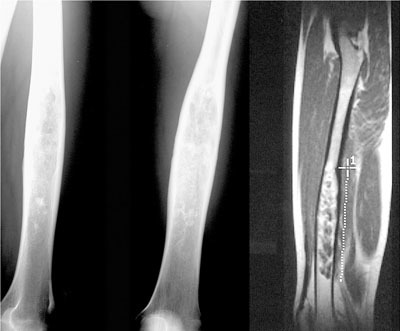

Quelle est la tumeur probable sachant qu’elle est maligne?

A

Tumeur épiphysaire à matrice cartilagineuse (pop corn) = chondrosarcome de l’extrémité sup du fémur